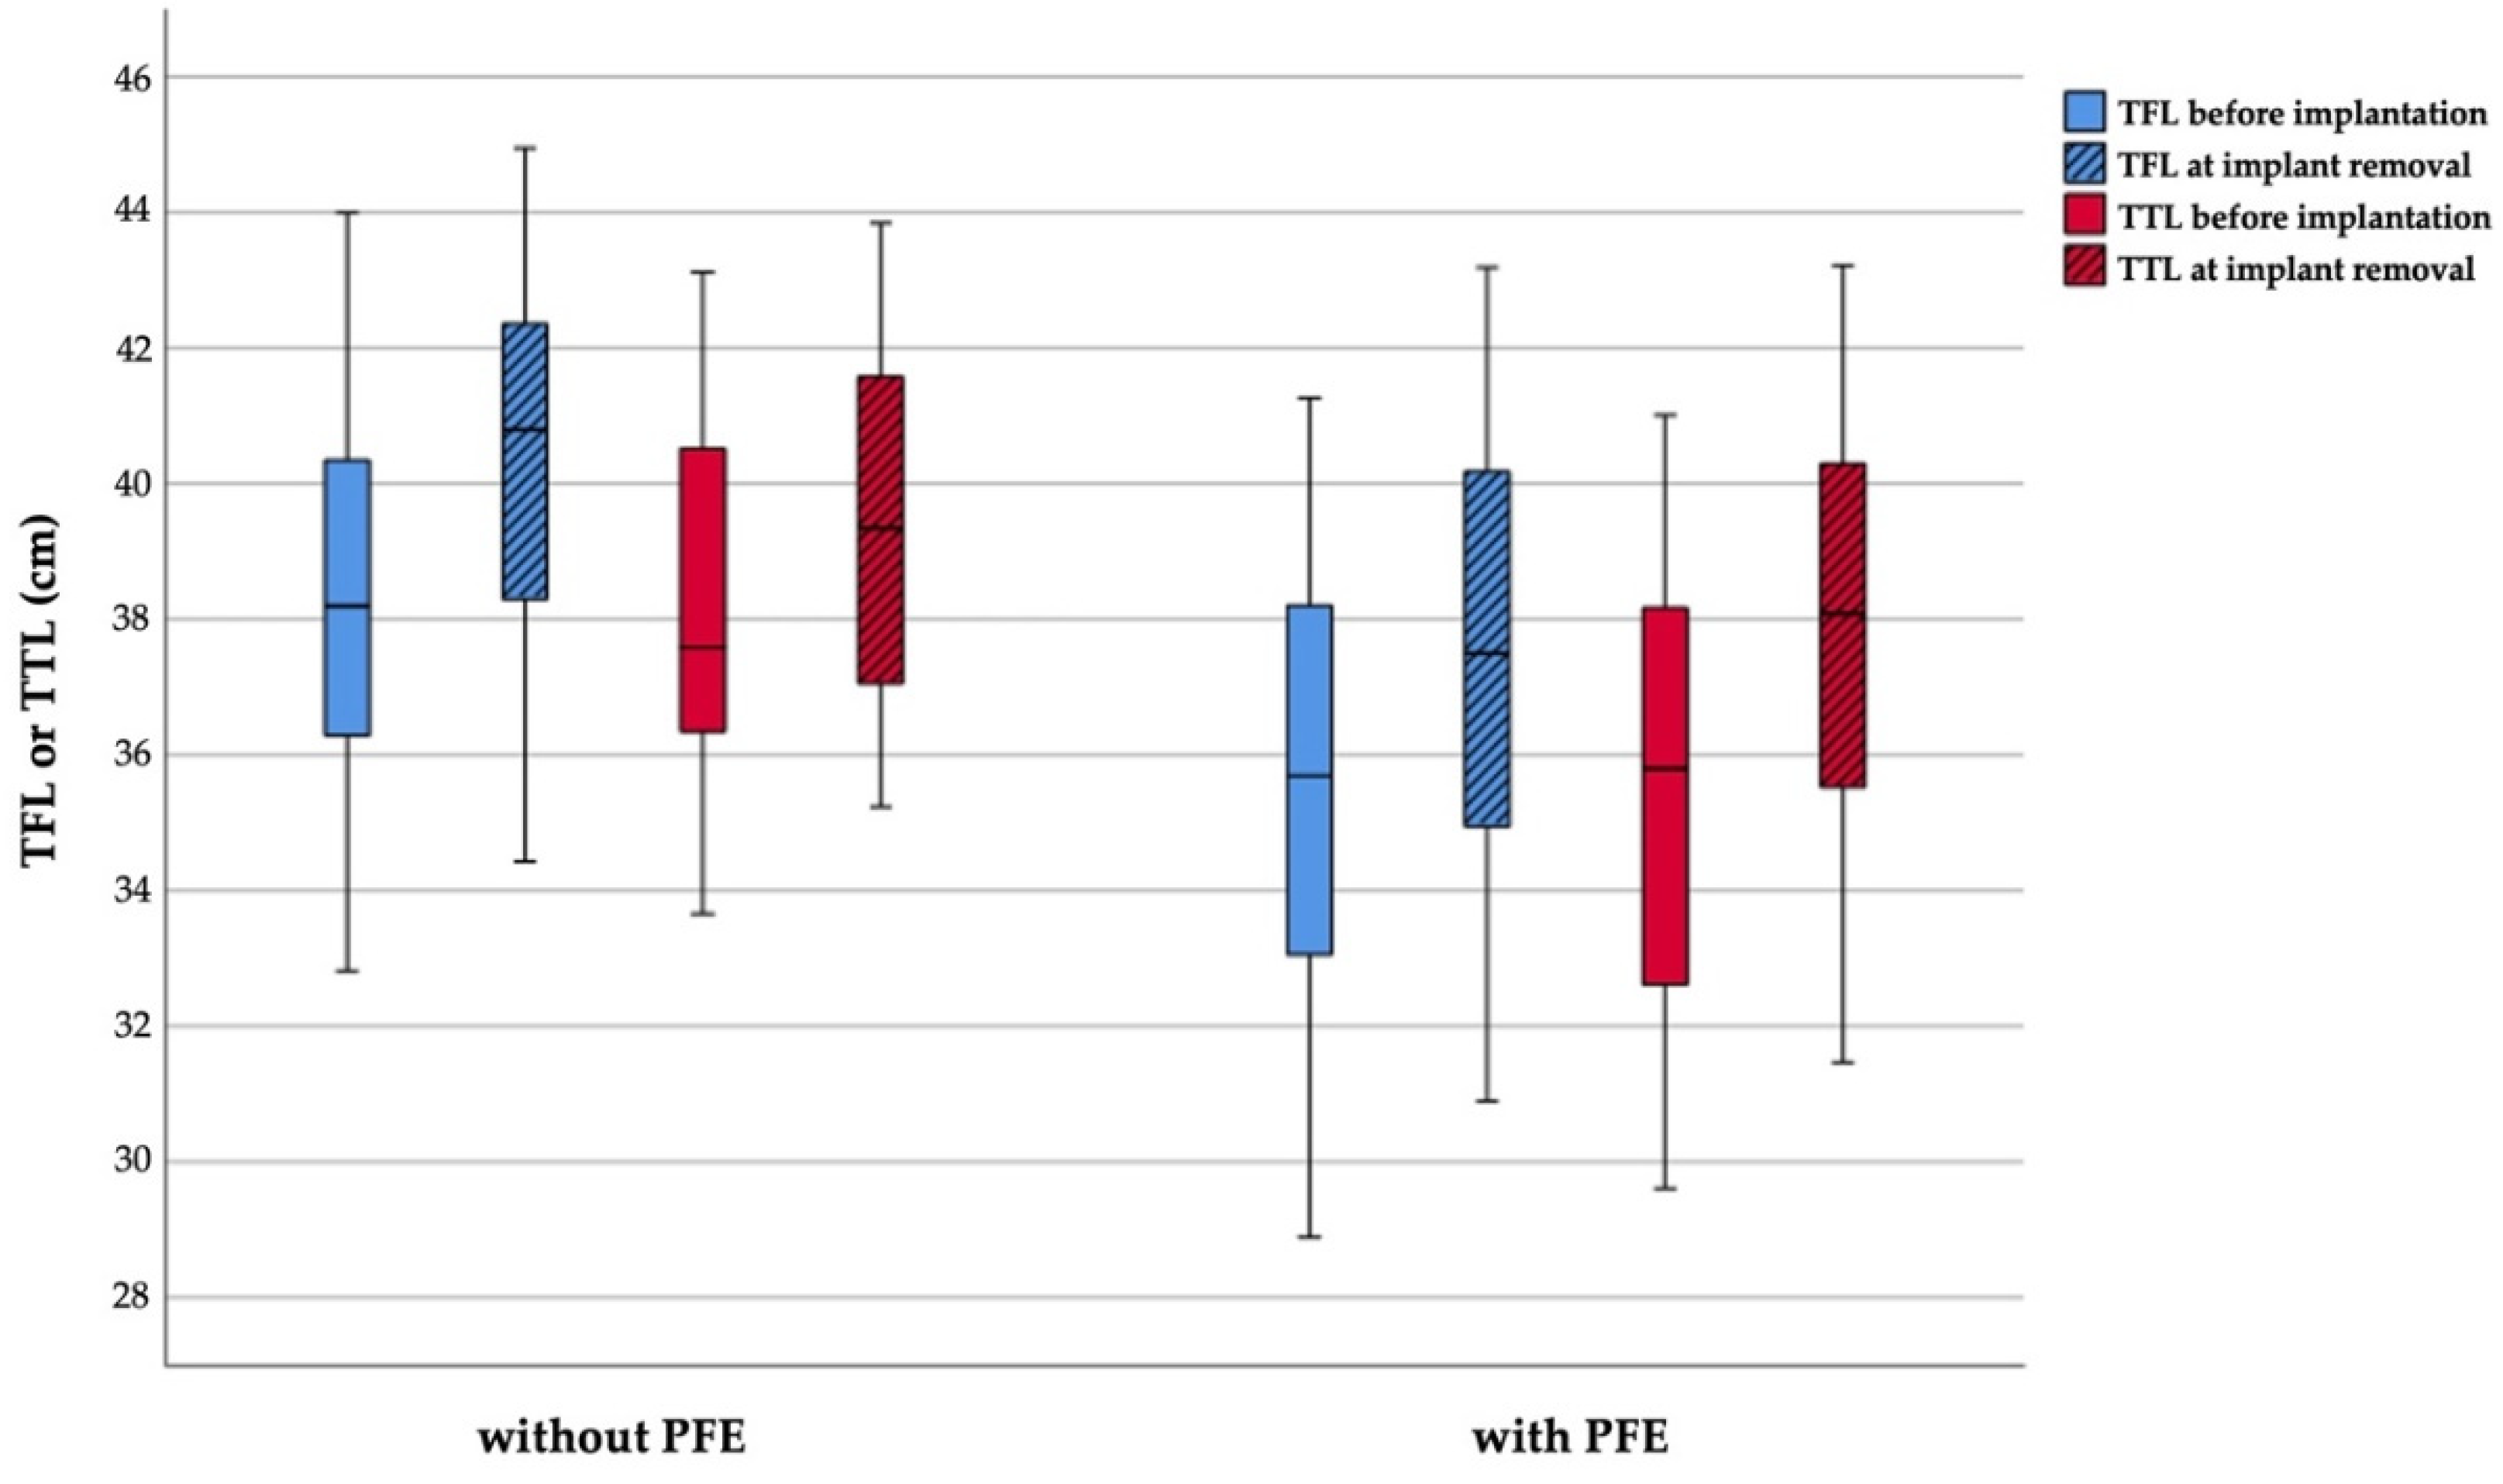

3.2. Radiographic Outcome Regarding Tibiofibular Relation

3.2.1. Comparison in Each of the Groups Treated with and without PFE

3.2.2. Comparison between the Groups Treated with and without PFE